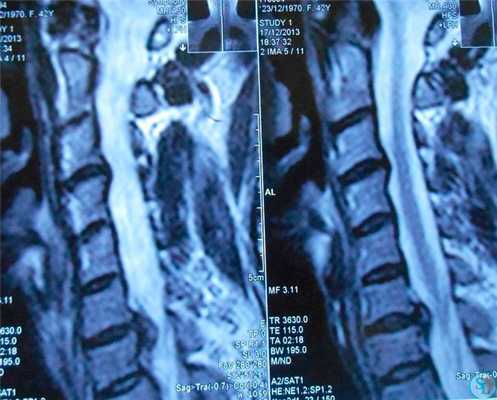

Миелопатия — это патология спинного мозга, которая возникает по различным причинам, в том числе из-за грыжи шейного отдела. В таком случае она называется вертеброгенная миелопатия. Хотя, справедливости ради, надо отметить, что именно из-за грыжи миелопатия возникает реже всего, но не надо с этим шутить. Основными симптомами миелопатии являются парезы, параличи и расстройства глубокой чувствительности. Иногда возникают нарушения функции тазовых органов. При обследовании пациентов большое значение имеют результаты МРТ. Они дают возможность увидеть, есть или нет сдавливание грыжей спинного мозга. Безоперационное лечение вертеброгенной миелопатии представляет собой мягкую мануальную терапию, ношение шейного корсета, физиопроцедуры и применение лекарственных препаратов. В тех случаях, когда консервативная терапия не приносит желаемого результата, рекомендуется хирургическое лечение.

Наиболее полную и точную информацию предоставляет МРТ. КТ может использоваться в качестве альтернативы только в легких случаях или при невозможности пациента оплатить стоимость магнитно-резонансной томографии. Исчерпывающие данные предоставляет исследование на томографе с напряженностью магнитного поля более 1,5 Тл. Благодаря снимкам МРТ удается досконально изучить вид, расположение и размер грыжи диска C6-C7, что позволяет подобрать оптимальную тактику лечения.

Магнитно-резонансная томография является основным и наиболее информативным методом диагностики грыж. С ее помощью можно не только подтвердить ее наличие, но и точно определить, какой диск поражен, а также измерить выпячивания с точностью до миллиметра, установить его вид, вовлеченность нервов в патологический процесс и дать прогноз о возможности секвестрации. Также благодаря МРТ удается оценить состояние других структур позвоночника и окружающих мягких тканей, т. е. обнаружить сопутствующие заболевания, наличие воспалительного процесса, атрофии мышц и другие нарушения.